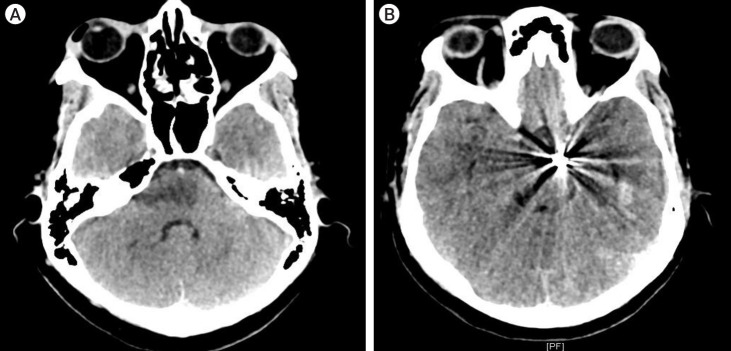

颅神经麻痹可能是颅内动脉瘤的先兆。动脉瘤血管与邻近神经之间存在典型的配对关系,从而导致颅神经病变。孤立的外展神经麻痹可能是未破裂的椎基底动脉循环动脉瘤的局部征兆。据报道,涉及小脑前下动脉(AICA)和小脑后下动脉(PICA)的动脉瘤与外展神经麻痹有关。未破裂动脉瘤的症状是由于邻近神经血管结构的肿块效应造成的。大多数外展神经麻痹在显微外科手术切除后可缓解。在此,我们介绍了一例罕见的未破裂的大脑后动脉(PCA)动脉瘤病例,该病例出现了外展神经麻痹和复视,并伴有对侧偏盲,经血管内线圈栓塞治疗后症状明显改善。

Cranial nerve palsies can be presenting signs of intracranial aneurysms. There is a classic pairing between an aneurysmal vessel and adjacent nerves leading to cranial neuropathy. Isolated abducens nerve palsy can be a localizing sign of an unruptured vertebrobasilar circulation aneurysm. Aneurysms involving Anterior Inferior Cerebellar Artery (AICA) and Posterior Inferior Cerebellar Artery (PICA) have been reported to be associated with abducens nerve palsy. The symptoms in unruptured aneurysms are due to the mass effect on adjacent neurovascular structures. Most of the abducens nerve palsy resolves following microsurgical clipping. Here, we present a rare case of an unruptured Posterior Cerebral Artery (PCA) aneurysm presenting with abducens nerve palsy and diplopia associated with contralateral hemianopsia which markedly improved following endovascular coil embolization.